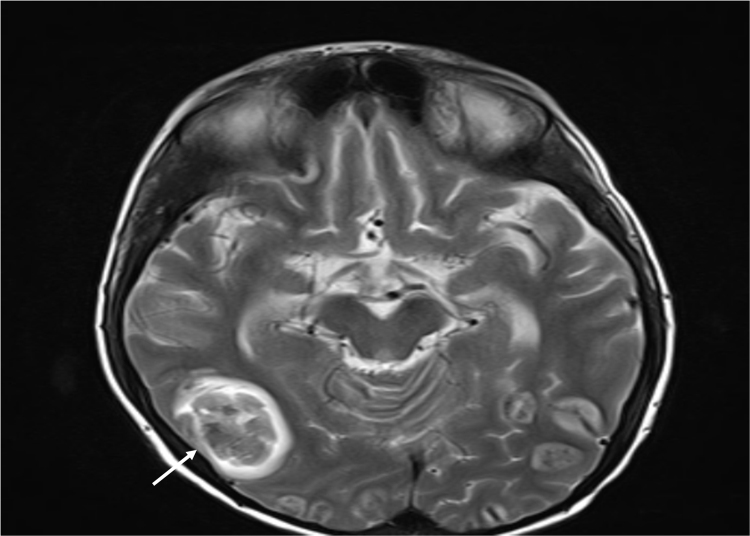

On the 9th day, the patient was unconscious and had convulsions, intraparenchymal multiple hemorrhagic abscesses were found on his second MRI which was performed four days later than the first MRI (Fig. 3). Histological examination of the biopsy specimen showed an aggregate of typical hypae of aspergillus spp with septae and branching at 45 angles (Fig. 4), and at the same time Galactomannan test was positive. These abscesses were evaluated as central nervous system involvement of invasive aspergillosis. Tests performed for immunoglobulin levels and flow cytometry immunophenotyping were normal.

Fig. 3.

Cranial MRI.

In CNS involvement, the brain lesions ranges from subtle abscesses, extensive hemorrhage, focal purulent meningitis and infarctions to massive hemorrhagic necrosis causing herniation and death. Single or multiple brain abscesses throughout the cerebrum, cerebellum, basal ganglia and brainstem are reported to be the most common sites of CNS aspergillosis (69.2%) [3]. In our patient, intraparenchymal multiple hemorrhagic abscesses were found on his second MRI and were evaluated as central nervous system involvement of invasive aspergillosis.